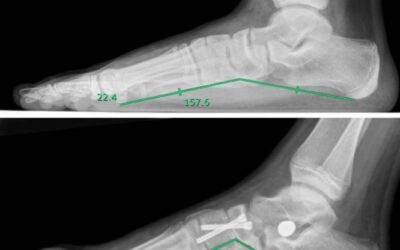

Positive Outcomes of Medial Arch and Hindfoot Reconstruction in Children

Although surgical alignment of the rear-foot might be sufficient to achieve acceptable correction of pronation-distortion deformity, concomitant correction of the medial arch might improve functional results. This study represents the authors’ experience with combined hind-foot alignment and medial arch reconstruction by in-situ naviculocuneiform arthrodesis for treatment of flexible flatfoot in children.